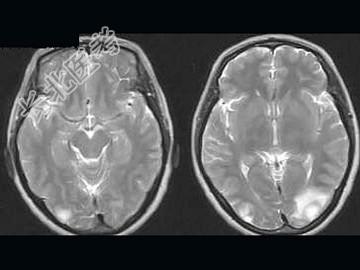

- 单项选择题女,52岁, 头晕2周,MRI检查如图, 最可能的诊断为 ( )

A、多发结核球

B、胶质瘤

C、囊性星形细胞瘤

D、脑内多发转移瘤

E、囊性淋巴瘤